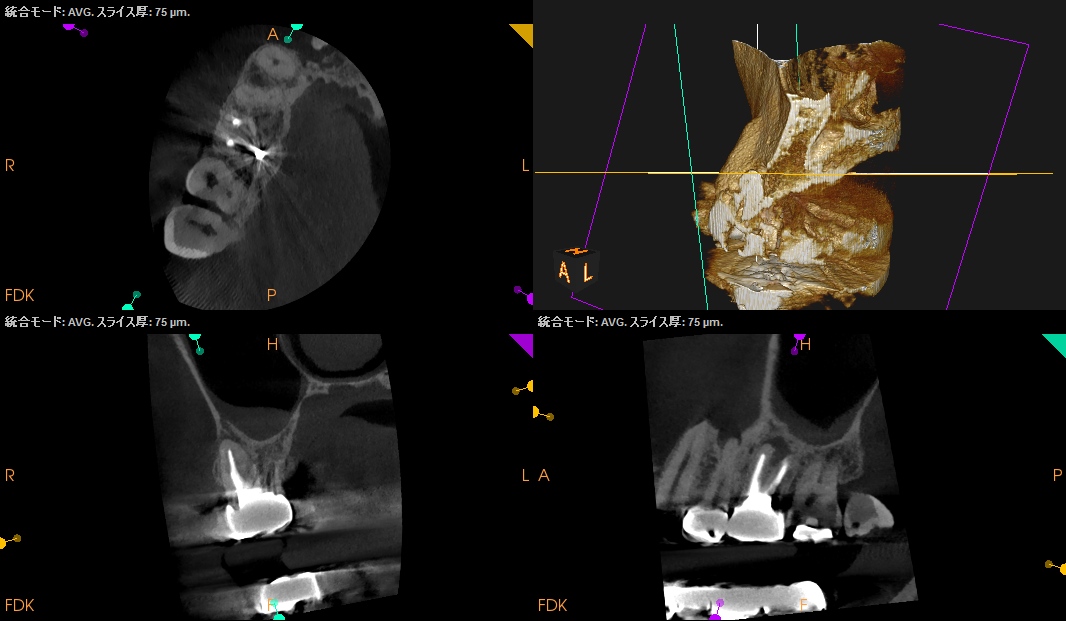

治療前の予測としては以下だ。

CEJよりも13mm先にApexがある。

が、この際にOsteotomyを行わなくてもApexには辿り着ける。

そしてApexから3mmで切断した時に、頬舌的には4.4mm削るだけで済む。

Very easyな外科治療だ。

そしてその際、Gutta PerchaがMBの中心にあることからこの根管は1根管であるということまでわかる。

まさにSuper easyなApicoectomyである。

このように

見れる・わかる・映りがいいCarestream社のようなCBCTがあれば, ここまで術前に予測ができるのである。